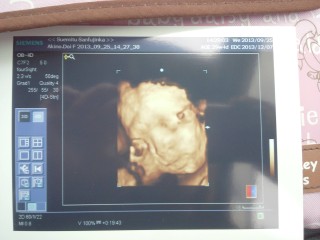

初の4Dで腕とかへその緒でお顔半分隠されちゃったけど、元気な姿見せてくれました!約1300gの女の子!どことなく旦那に似てるかな。笑

4D映像がすごい!こんなにはっきり映るのがびっくりしました。2人目ですけど、やっぱり感動しました!1540g元気な女の子です!もうすぐ会えるよ~